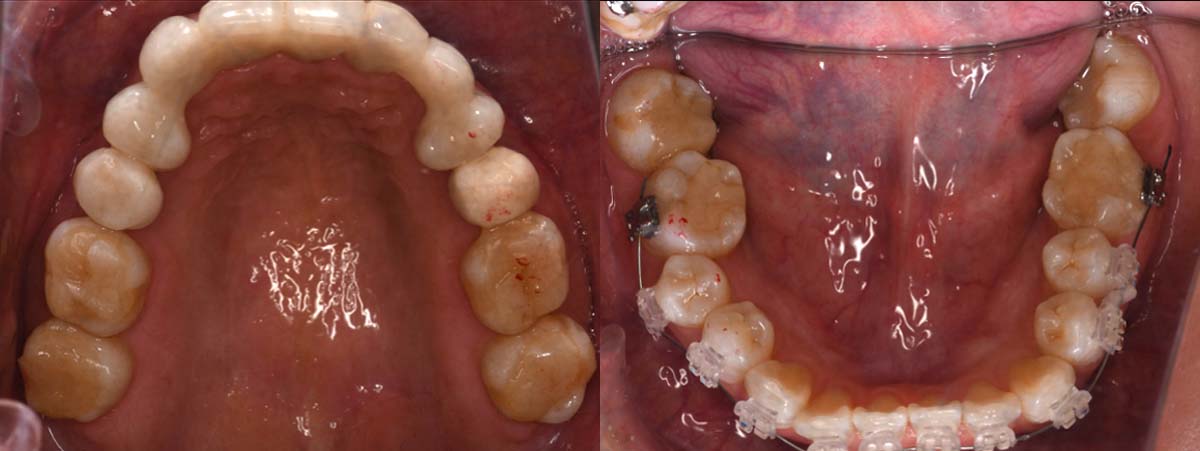

2024年 10月 下顎MTM開始

2024年 10月10日

10月21日

11月7日

11月28日

12月16日

12月23日

1月9日

1月30日

2月20日

3月13日

4月24日

9月25日